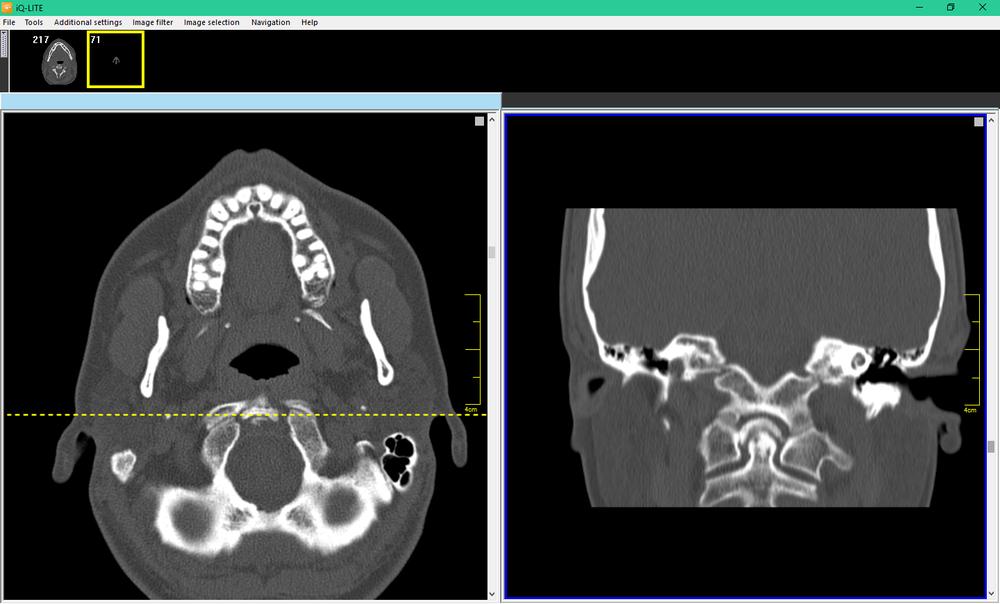

The disk containing the DICOM data came with a lightweight viewer, and allowed me to look at individual slices from the CT scan. The scan focused on the nasal cavities, and extended nearly to the back of the skull. I ended up with a complete set of images from the forehead down to to most of the lower jaw.

CT Scan: White areas are bone structures[/caption]